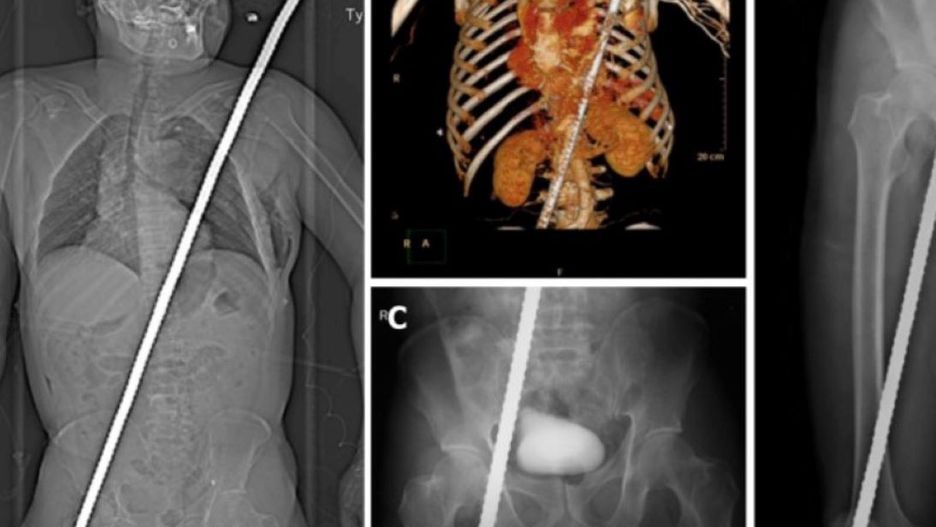

56-letni mężczyzna spadł z wysokości 3 metrów i nadział się na dwumetrowy pręt zbrojeniowy. Pręt przebił praktycznie całe ciało Chińczyka - wbił się przez udo i wyszedł w okolicy ramienia. Zdjęcia ukazujące pacjenta wyglądają naprawdę wstrząsająco.

Tomografia komputerowa i zdjęcia rentgenowskie ciała wykazały, że pręt zbrojeniowy przechodził przez lewą stronę klatki piersiowej, tuż obok serca. Pacjent mógł więc mówić o dużym szczęściu, gdyż pręt cudem ominął kluczowe organy.

Stwierdzono złamania żeber, odmę opłucnową, pęknięcie osierdzia i przepony oraz urazy żołądka i ściany jelita, nie wykluczając pęknięcia lewego płata wątroby i perforacji przewodu pokarmowego. Oszczędzono wielkie naczynia klatki piersiowej, a lewe płuco i osierdzie zostały poranione i stłuczone - czytamy na facebookowym profilu "Ratownictwo Medyczne - łączy nas wspólna pasja".